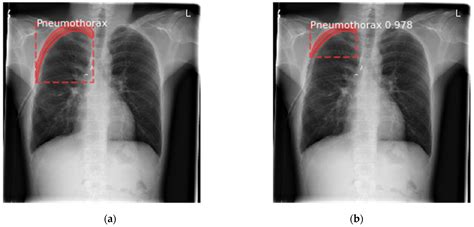

Diagnosing Pneumothorax with Chest X-Ray

Chest X-rays are the primary imaging modality used to diagnose pneumothorax. They provide a clear view of the lungs and pleural space, allowing radiologists to identify the presence of air. The key features to look for in a pneumothorax in X-ray include:

• The absence of lung markings beyond the visible edge of the collapsed lung

• A visible line representing the edge of the collapsed lung

• Hyperlucency (increased brightness) in the affected area

• Deviation of the mediastinum (the central compartment of the thorax) towards the unaffected side

Interpreting Pneumothorax in X-Ray

Interpreting a pneumothorax in X-ray requires a systematic approach. Here are the steps to follow:

1. Assess the Overall Quality: Ensure the X-ray is of good quality, with clear visualization of the lungs and pleural spaces.

2. Identify the Visible Edge: Look for the visible edge of the collapsed lung, which appears as a thin, sharp line.

3. Check for Lung Markings: Note the absence of lung markings beyond the visible edge.

4. Evaluate Hyperlucency: Assess the area of increased brightness, which indicates the presence of air in the pleural space.

5. Examine the Mediastinum: Check for any deviation of the mediastinum towards the unaffected side, which may indicate a tension pneumothorax.